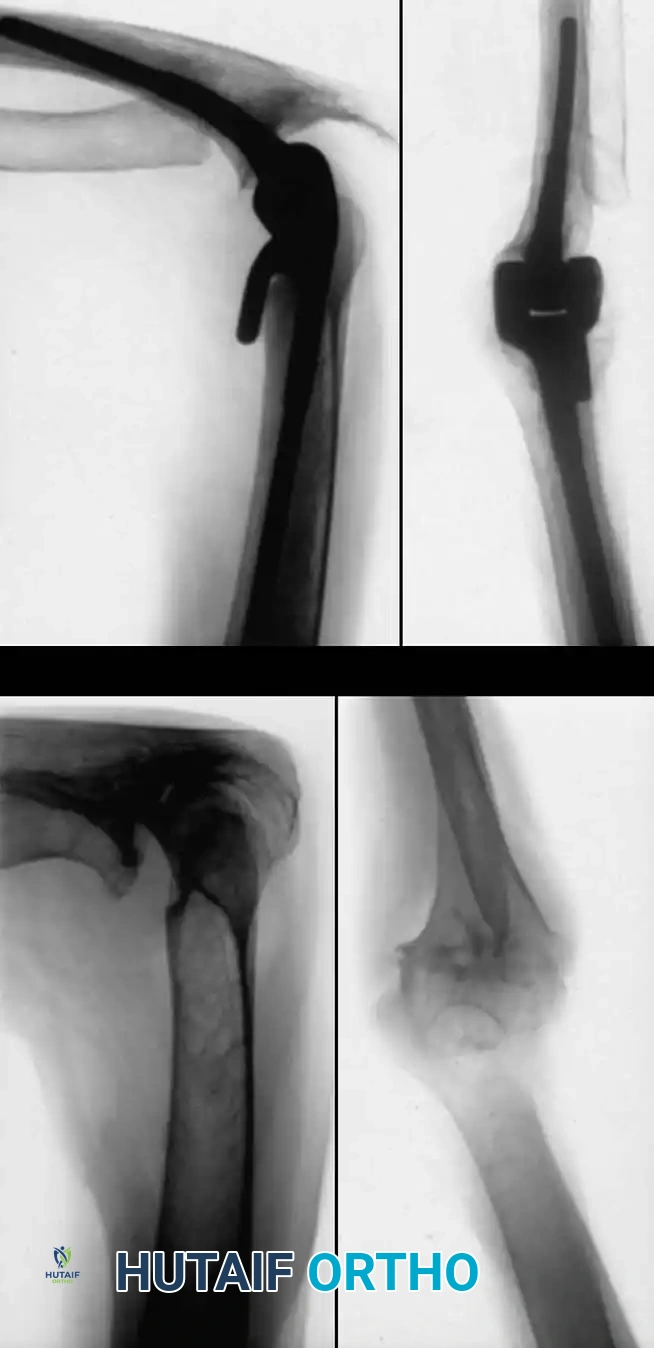

Total Elbow Arthroplasty (TEA)

The most common diagnosis for which total elbow arthroplasty is performed is rheumatoid arthritis, yielding satisfactory results in approximately 90% of patients.

Outcomes and Evidence:

* Ewald et al. reported on 202 capitellocondylar prostheses with a 2- to 15-year follow-up. Pain relief and functional improvement were excellent (average score improved from 26 to 91 on a 100-point scale). Reoperation for loosening, dislocation, or infection occurred in only 5%.

* Inglis and Figgie reported 77% good or excellent results in 137 semiconstrained total elbow replacements for RA.

* Gill and Morrey demonstrated a 92.4% survival rate at 10 to 15 years using the Mayo modified Coonrad semiconstrained prosthesis.

Surgical Warning: When performing TEA, meticulous handling of the ulnar nerve is mandatory. Routine ulnar nerve transposition is often performed to prevent postoperative neuropathy, especially in patients with pre-existing flexion contractures.